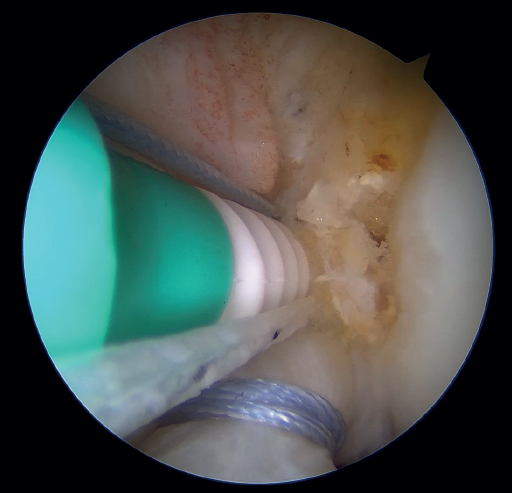

Once a good view of the central compartment is obtained, the area of the femoral footprint of the ACL is prepared to leave exposed bone, and microperforations are made in the medial wall of the lateral condyle to leave a bleeding bed to favor healing of the ligament (Figure 3). These microperforations can be made using specific instruments or with the implant punch. The advantage of using the punch is that the implant insertion site can be prepared at the same time, and only one instrument is used for the entire process (Figure 4). This step can be done after the suture has been prepared in the ligament, although doing it beforehand avoids the threads from standing in the way. The ideal point for fixation is just anterior to the native ACL footprint, although if the tear is partial or corresponds to Sherman I, it can be taken to the anatomical footprint without difficulty.

The next step consists of introducing the necessary instruments through the anteromedial portal to make several perforations approximately 1 mm deep in the femoral insertional footprint, with the aforementioned aim of obtaining a bleeding bed to facilitate healing of the ACL. Such drilling can be done manually (with micro- or nanofracture punches) or motorized (PowerPick®, Arthrex), and this step is usually made easier by flexing the knee at about 100°.

The femoral tunnel is made from this accessory medial portal using a 4.5 mm diameter spear point drill, from the most anterior portion of the insertional footprint of the ACL through the lateral cortex of the femur. Once the tunnel has been completed, the same drill is used to leave a retriever thread through the femoral tunnel, as it is equipped with an eyelet. It is important to secure the two ends of this thread together outside of the knee in order to avoid losing either of them during surgery.